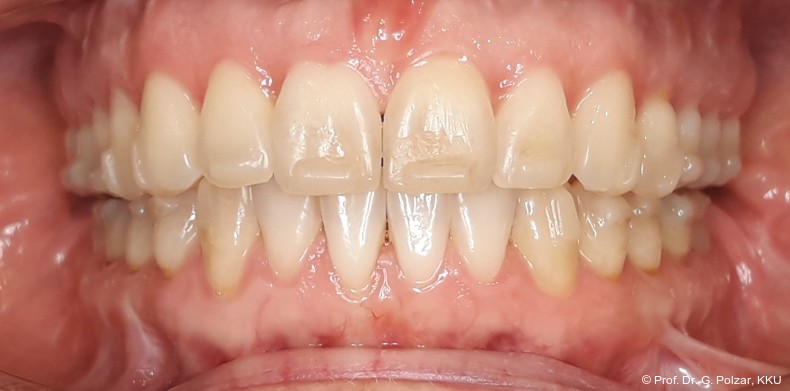

Der intraorale Befund zeigte eine scheinbar neutrale Verzahnung. Trotz Lingualretainer in der UK-Front war ein Engstand in der Unterkieferfront mit leichter Protrusion erkennbar. Appro­ximal des Zahnes 41 waren deutliche schwarze Dreiecke zu erkennen, zudem wies der Zahn eine leichte gingivale Rezession auf (Abb. 3a–f).

Diese deutlich anteriore Gelenkposition im Neutralbiss ließ den Verdacht auf einen Sunday Bite zu. Das heißt, die Patientin schob den Unterkiefer aktiv nach vorne, um damit schönere Schneidezahnkontakte bzw. eine vermeintlich neutrale Okklusion zu erreichen. Nach mühsamen Lockerungsübungen gelang es der Patientin, auch in die zen­trale Kiefergelenkposition zu wechseln. So zeigte sich das ganze Ausmaß der Malokklusion. In neutraler KG-Position hatte die Patientin eine sagittale Frontzahnstufe von ca. 7 mm mit 1 PB Klasse II-Okklusion im Seitenzahn­bereich (Abb.5a+b, 7a–c).